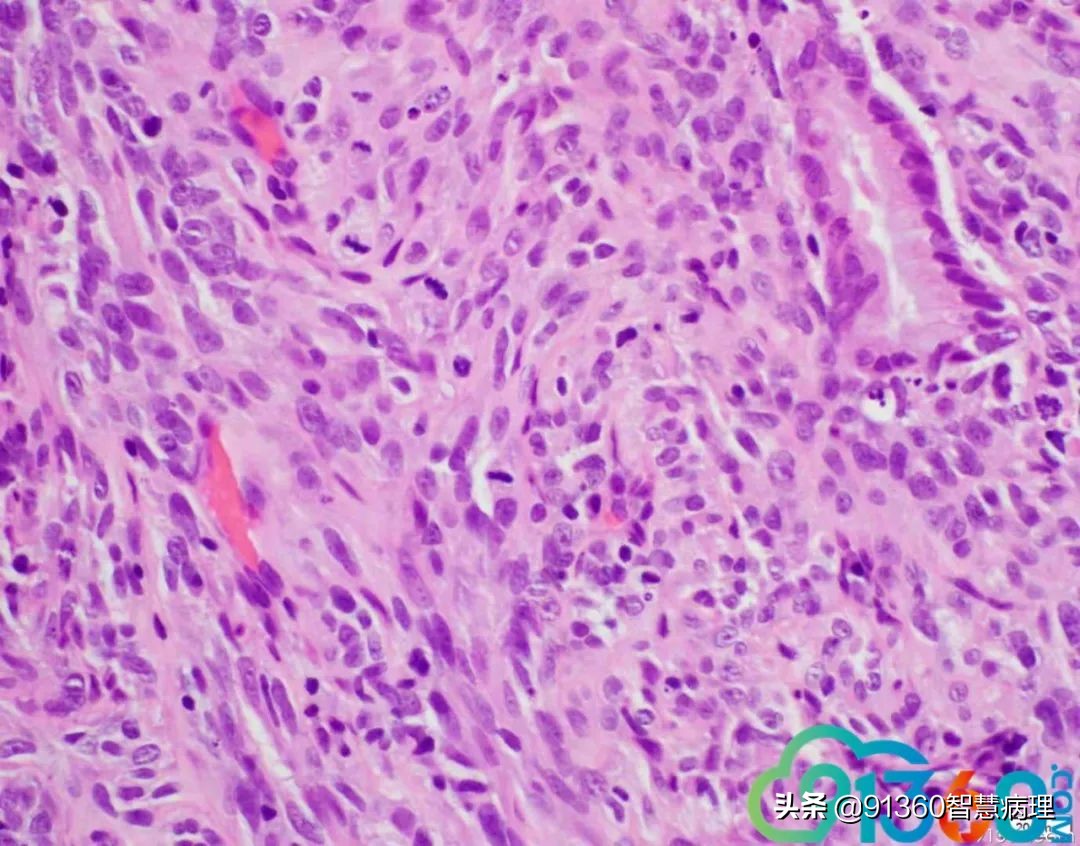

邢德印 Desmin -Sarcomatoid carcinoma; spindle cell carcinoma 石岩 @邢德印(妇科病理) 好例子 邢德印 以前没见过这么明显的,太肉瘤样了 任永昌 @邢德印(妇科病理) 赞 郭晓静 @邢德印(妇科病理) 我偏向猜的答案也是这个,。谢谢分享! 王昀 @邢德印(妇科病理) 好例子,没见过这么弥漫肉瘤样的,回过头来看,好像还是有点结构的样子

邢德印 @王昀 301 圈里的是mitosis 任永昌 @邢德印(妇科病理) @王昀 301 实际上,上边这个腺体有异型,核过于大。

王昀 哦,我说那个裂隙,有点像腺的结构 邢德印 @临沂市中心医院任永昌 @王昀 301 腺体其实是entrapped,正常的腺体 王昀 我是想起乳腺的化生性癌,所以想看看有没有腺和梭形细胞过渡移行的地方,能找点线索,可能是知道答案后开始想象了,这个可能是假腺